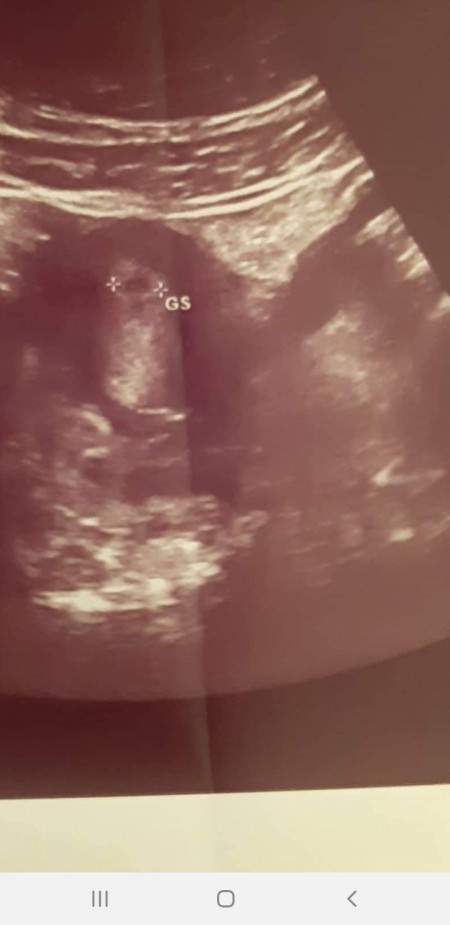

Kalp şeklinde rahim teşhisini koymak için 3 boyutlu bir ultrason ve basit bir rahim filmi yeterlidir. En ciddi rahim anomalisidir. Düşük yapsaydi ameliyat olacakti sanirim. Rahim kubbesinde hafif bir çökkünlük vardır.